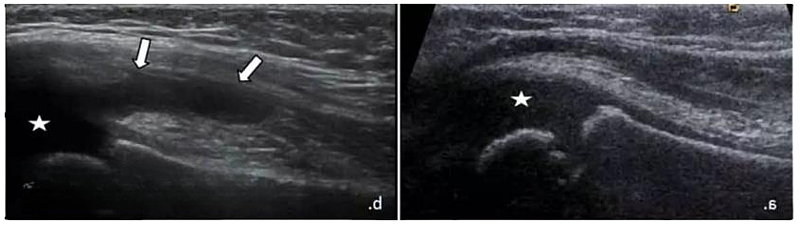

腕部较大腱鞘囊肿(*)压迫正中神经(a中空箭头,b中MN)

◾周围神经病变的“洞察者”:神经卡压、病变的微妙变化,也逃不过它的敏锐目光。